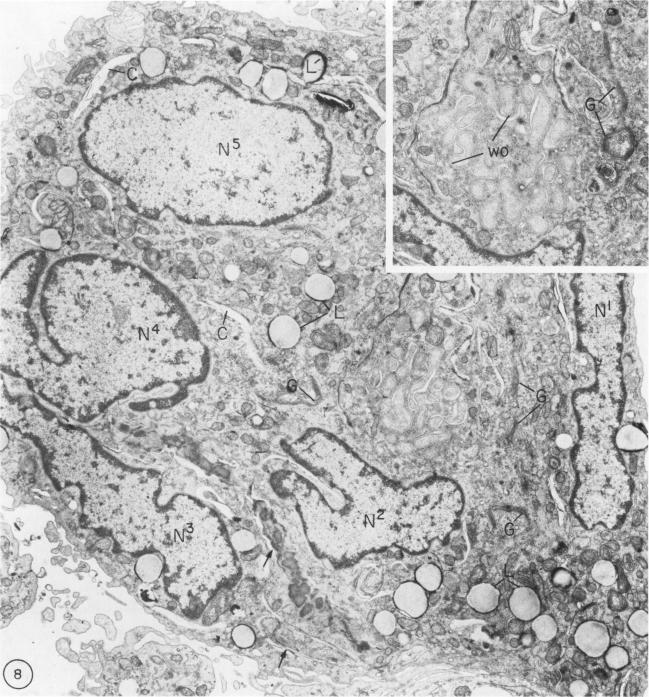

To study the various stages of human mononuclear phagocyte maturation, we cultivated bone marrow in an in vitro diffusion chamber with the cells growing in suspension and upon a dialysis membrane. At 2, 7, and 14 days, the cultured cells were examined by electron microscopy and cytochemical techniques for peroxidase and for more limited analysis of acid phosphatase and arylsulfatase. Peroxidase was being synthesized in promonocytes of 2- and 7-day cultures, as evidenced by reaction product in the rough-surfaced endoplasmic reticulum, Golgi complex, and storage granules. Peroxidase synthesis had ceased in monocytes and the enzyme appeared only in some granules. By 7 days, large macrophages predominated, containing numerous peroxidase-positive storage granules, and heterophagy of dying cells was evident. By 14 days, the most prevalent cell type was the large peroxidase-negative macrophage. Thus, peroxidase is present in high concentrations in immature cells but absent at later stages, presumably a result of degranulation of peroxidase-positive storage granules. Clusters of peroxidase-negative macrophages with indistinct borders (epithelioid cells), as well as obvious multinucleated giant cells, were noted. Frequently, the interdigitating plasma membranes of neighboring macrophages showed a modification resembling a septate junction--to our knowledge, representing the first documentation of this specialized cell contact between normal macrophages. We suggest that such junctions may serve as zones of adhesion between epithelioid cells.

为了研究人类单核吞噬细胞成熟的各个阶段,我们在体外扩散小室中培养骨髓,细胞在悬浮状态下以及透析膜上生长。在第2天、第7天和第14天,通过电子显微镜和细胞化学技术对培养的细胞进行过氧化物酶检测,并对酸性磷酸酶和芳基硫酸酯酶进行更有限的分析。在培养2天和7天的原单核细胞中可检测到过氧化物酶的合成,粗面内质网、高尔基体复合体和储存颗粒中的反应产物可证明这一点。单核细胞中过氧化物酶的合成已经停止,该酶仅出现在一些颗粒中。到第7天时,大型巨噬细胞占主导地位,含有大量过氧化物酶阳性储存颗粒,并且明显可见对死亡细胞的异噬作用。到第14天时,最普遍的细胞类型是大型过氧化物酶阴性巨噬细胞。因此,过氧化物酶在未成熟细胞中浓度较高,但在后期阶段不存在,推测这是过氧化物酶阳性储存颗粒脱颗粒的结果。注意到边界不清晰的过氧化物酶阴性巨噬细胞簇(上皮样细胞)以及明显的多核巨细胞。相邻巨噬细胞相互交错的质膜经常显示出一种类似于分隔连接的改变——据我们所知,这是正常巨噬细胞之间这种特殊细胞接触的首次记录。我们认为这种连接可能作为上皮样细胞之间的黏附区域。